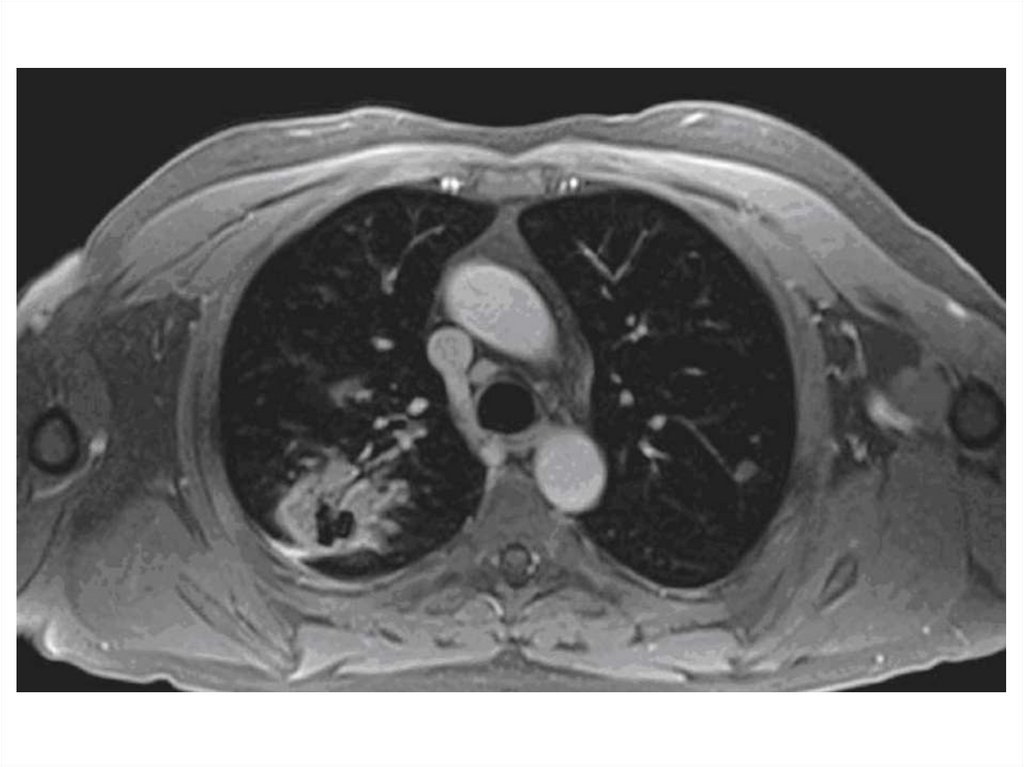

МРТ

17.